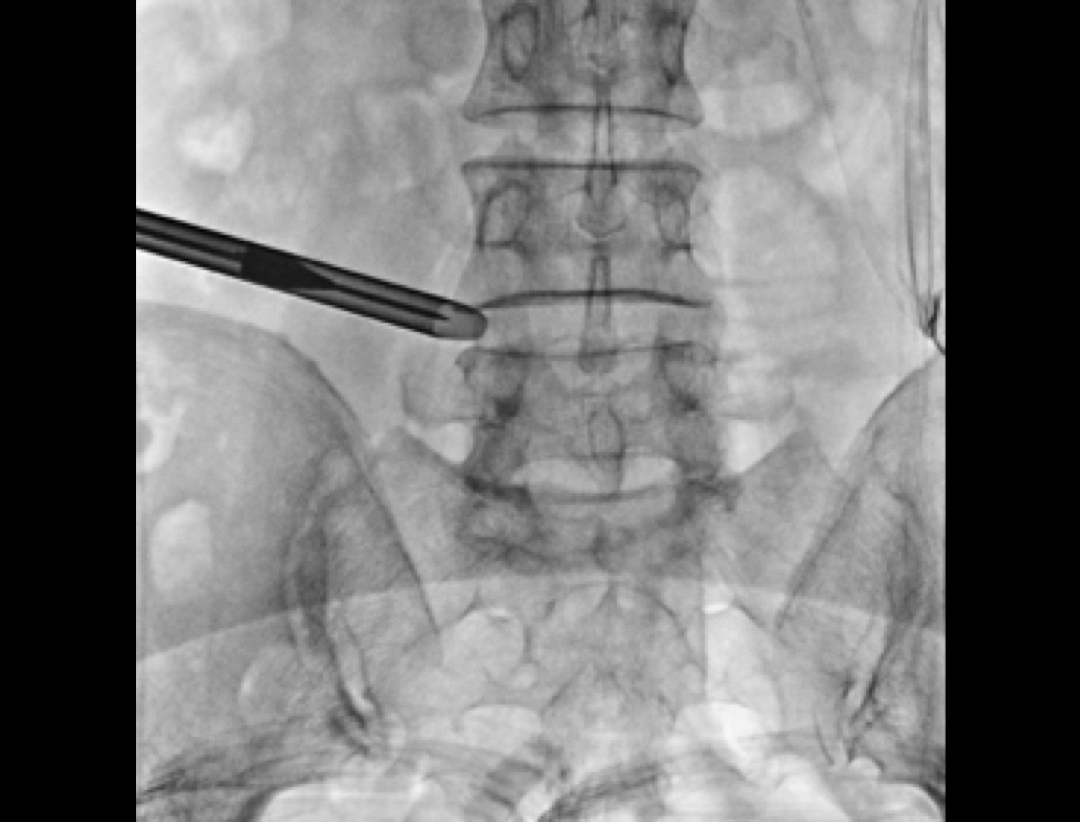

Kyfoplastyka przezskórna